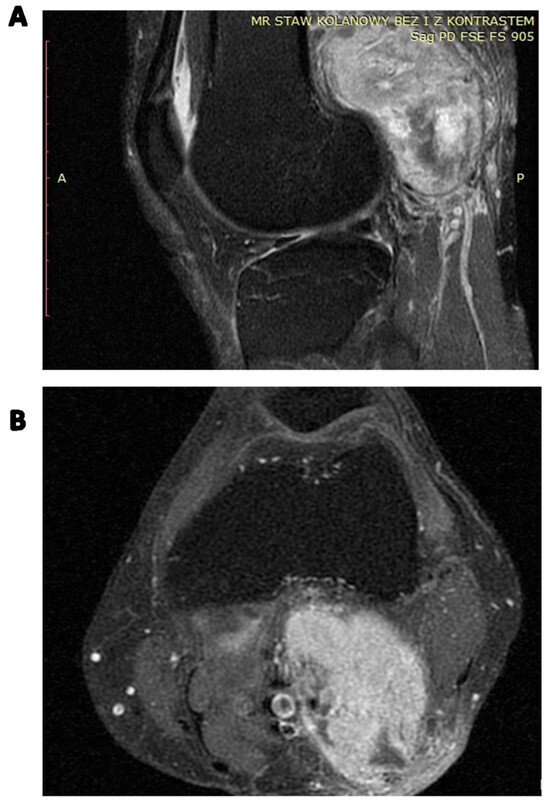

- Öztürk, R.; Arıkan, Ş.M.; Şimşek, M.A.; Özanlağan, E.; Güngör, B. Management of solitary fibrous tumors localized in extremity: Case series and a review of the literature. Eklem Hastalik. Cerrahisi 2017, 28, 121–127. [Google Scholar] [CrossRef]

- Chandanwale, S.S.; Gore, C.R.; Sammi, A.B.; Shah, K.R.; Kaur, P.R. Recurrent solitary fibrous tumor in distal lower extremity: An extremely rare entity. Int. J. Appl. Basic Med. Res. 2014, 4, 134–136. [Google Scholar] [CrossRef]

- Akisue, T.; Matsumoto, K.; Kizaki, T.; Fujita, I.; Yamamoto, T.; Yoshiya, S.; Kurosaka, M. Solitary fibrous tumor in the extremity: Case report and review of the literature. Clin. Orthop. Relat. Res. 2003, 411, 236–244. [Google Scholar] [CrossRef]

- Lee, J.Y.; Kim, D.H.; Seo, K.J.; Jung, S.N. A Solitary Fibrous Tumor (Cellular Form) of the Ankle. J. Foot Ankle Surg. 2016, 55, 829–831. [Google Scholar] [CrossRef]

- Bianchi, G.; Sambri, A.; Pedrini, E.; Pazzaglia, L.; Sangiorgi, L.; Ruengwanichayakun, P.; Donati, D.; Benassi, M.S.; Righi, A. Histological and molecular features of solitary fibrous tumor of the extremities: Clinical correlation. Virchows Arch. 2020, 476, 445–454. [Google Scholar] [CrossRef] [PubMed]